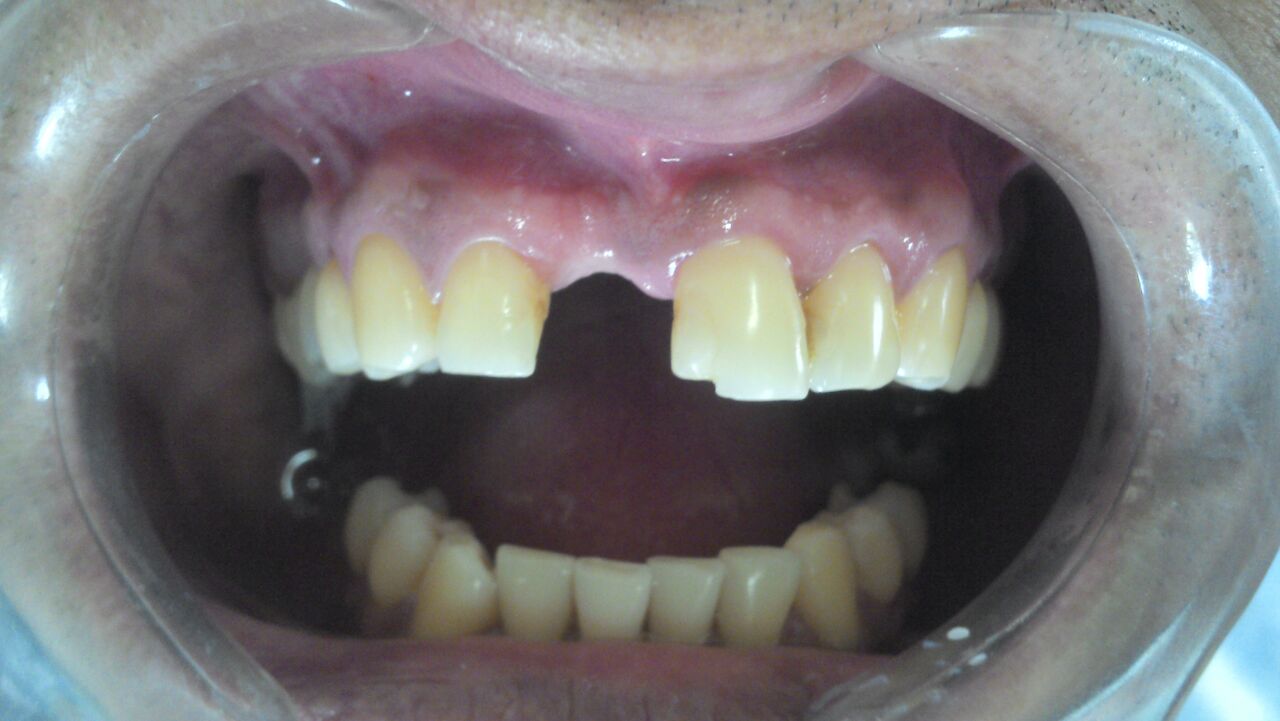

Observem: nesse caso o paciente perdeu o incisivo central superior direito e necessitava de um implante dentário.

Porém, quando se perde um dente, o nosso organismo reabsorve o osso alveolar e ele fica menor em altura e espessura.